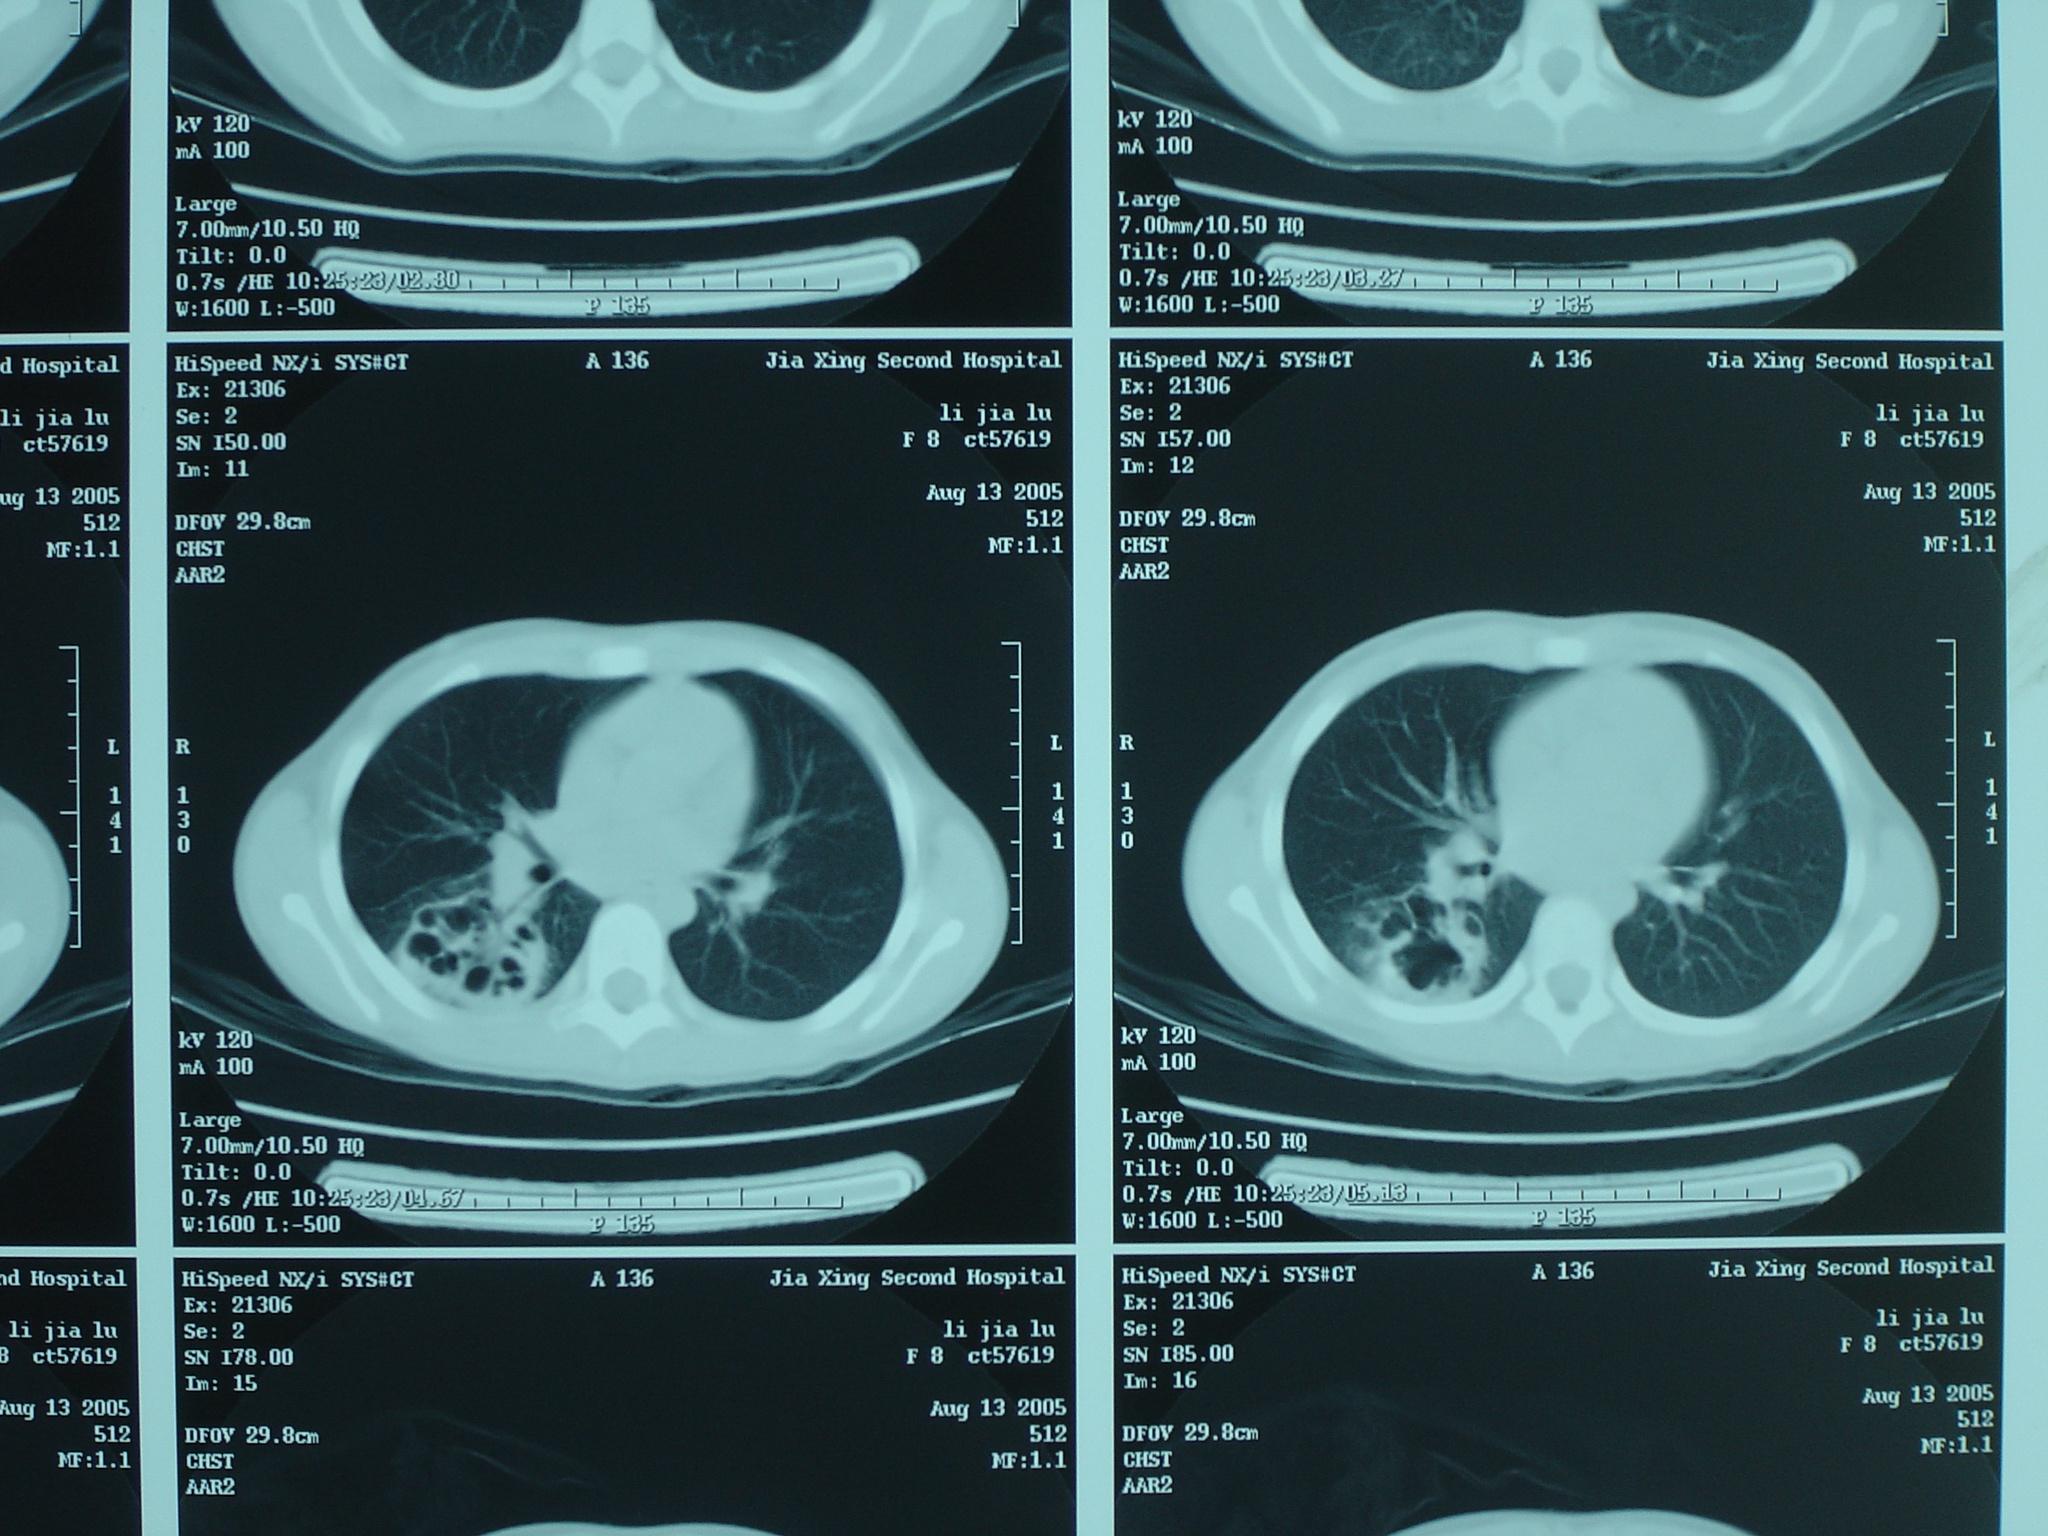

【讨论】肺脓疡?

肺脓肿-ct(图)

肺脓肿